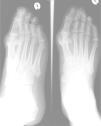

Laboratory tests showed uricemia of 9.4mg/dl and GGT 166U/dl. The remaining parameters (CBC, TSH, CPK, rheumatoid factor, HLA B27, anti-CCP antibodies, immunoglobulins, 24h urine uric acid) were normal. X-rays of the left foot were performed (Fig. 1), showing marginal erosions and sclerotic borders of the first metatarsal head, with increased adjacent soft tissue. A left knee radiograph (Fig. 2) showed lytic lesions with well-defined edges and incipient degenerative changes of the tibial epiphysis at the femorotibial level. We performed arthrocentesis of the left knee. Monosodium urate crystals were found in synovial fluid (SF). SF culture was negative.